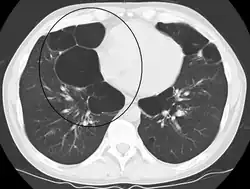

| Advanced centrilobular emphysema showing total lobule involvement on the left side | |

Centrilobular

Centrilobular emphysema, also called centriacinar emphysema, affects the centre of a pulmonary lobule (centrilobular) in the lung, the area around the terminal bronchiole and the first respiratory bronchiole, and can be seen on imaging as an area around the tip of the visible pulmonary artery. Centrilobular emphysema is the most common type usually associated with smoking, and with chronic bronchitis.[17] The disease progresses from the centrilobular portion, leaving the lung parenchyma in the surrounding (perilobular) region preserved.[23] Usually the upper lobes of the lungs are affected.[17]